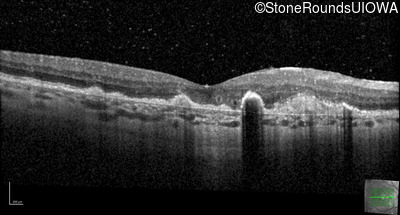

Malattia Leventinese (IIJ)

Malattia Leventinese (IIJ)

This 43 year old woman has experienced a gradual reduction in her central vision for the past 3 years.

| Malattia Leventinese | EFEMP1 | Arg345Trp CGG>TGG | AD |